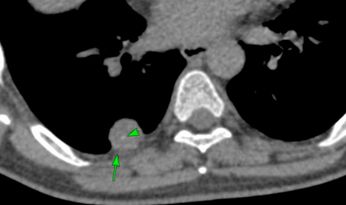

Case 34: All High-Density Foci in the Lungs Are Not Old Calcified Granulomas Paid Members Public

All high-density foci in the lungs are not old calcified granulomas